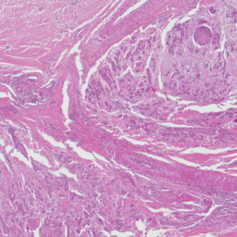

2 Materials

Our experiments were performed on the squamous cell carcinoma (SCC) subset of the publicly available CATCH dataset [11]. Use of these samples was approved by the local governmental authorities (State Office of Health and Social Affairs of Berlin, approval ID: StN 011/20). The specimens were originally digitized with the Aperio ScanScope CS2 (Leica, Germany) at a resolution of using a objective lens. To create a multi-scanner dataset with local correspondences, we digitized the samples with four additional slide scanners (exemplary patches in Figure 1) :

(a) CS2

(b) NZ 210

(c) NZ 2.0

(d) P 1000

(e) GT 450